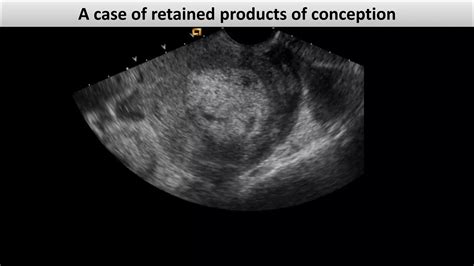

Medical professionals typically employ a multi-modal approach to confirm the presence of Retained Products Conception. Because symptoms can mimic other postpartum or post-miscarriage conditions, imaging is usually the gold standard for diagnosis.

Transvaginal Ultrasound Used to visualize the uterine cavity and identify echogenic masses that indicate retained tissue.